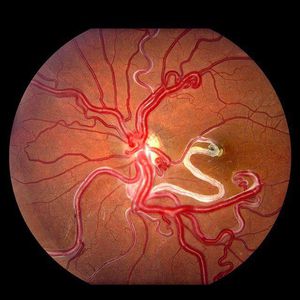

Wuyburn Mason's Syndrom (Eye)

Ophthalmology